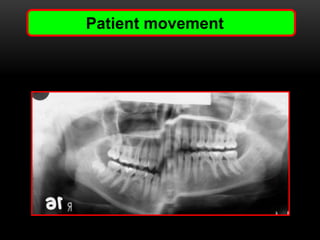

Patient movement

• #43 If the pt moves while taking an opg it results in distorted image